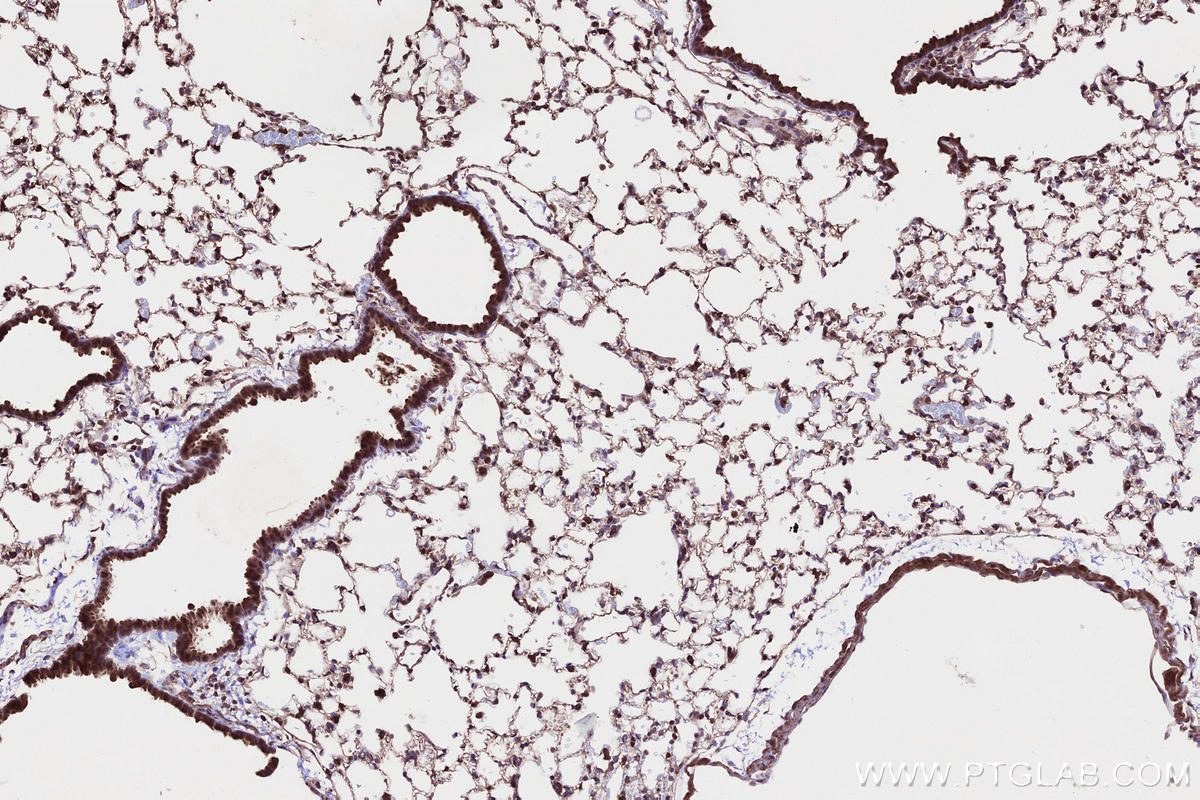

Validation Data Gallery